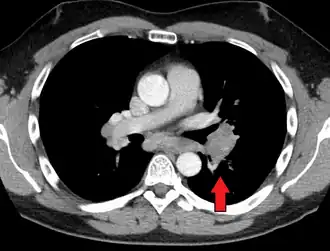

Hilar adenopathy especially on the person's left (AP CXR)

Hilar adenopathy especially on the person's left (transverse CT)